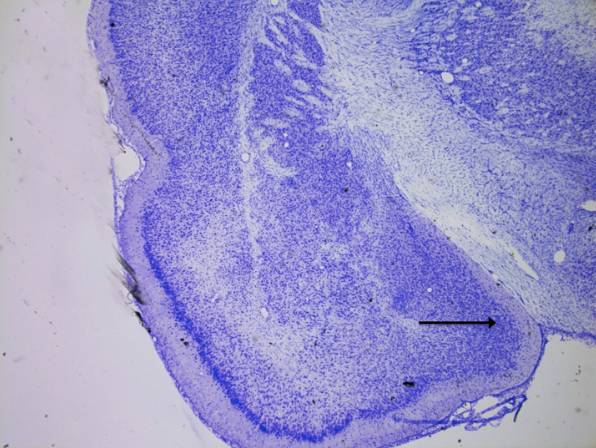

Nucleus accumbens

knowt flashcard image